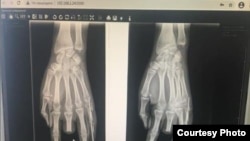

Гуля Белек кызынын жабыркаган колунун рентгенге түшүрүлгөн сүрөтү.

Жакында эле Гулянын колуна операция жасалып, Илизаров аппараты коюлду. Аны апрелдин орто ченинде алышат. Ал эми кесилген манжанын ордуна жасалма бионикалык манжа тагуу зарыл. Абдиеванын айтымында, андай жасалма манжа бери дегенде 1,5 миллион рубль турат.